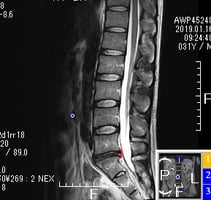

椎間板ヘルニア

2年前から腰痛を感じ少しずつ悪化、1年前に整形外科を受診し、MRI検査で椎間板ヘルニアと診断される。

フラットバック(腰椎前弯消失)・腰椎減圧・仙腸関節・特に股関節の柔軟性向上ストレッチ